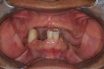

Combination syndrome

The clinical changes observed when an edentulous maxillary arch is opposed by a mandible with retained anterior teeth that may or may not be extruded and missing posterior teeth. Over time, there is a loss of bone in the premaxilla and in the edentulous posterior mandible, overgrowth of the maxillary tuberosities, and hyperplasia of the…